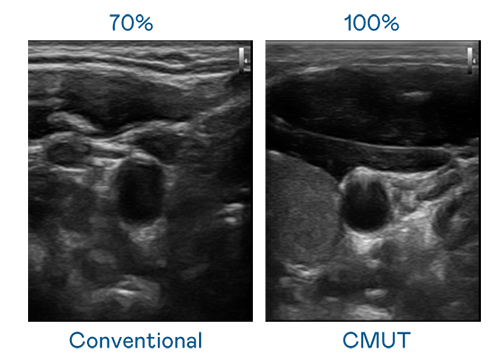

申博太陽(yáng)城運(yùn)用 TFT 陣列 (Array) 制程延伸尖端感測(cè)技術(shù) ,開(kāi)發(fā)出多種感測(cè)元件的產(chǎn)品。高解析度、品質(zhì)穩(wěn)定且可量產(chǎn)的 CMUT 元件,可制作高解析度超音波探頭、貼片型探頭 ,對(duì)病患實(shí)施精準(zhǔn)檢測(cè)與長(zhǎng)時(shí)間生理監(jiān)測(cè) 。為滿(mǎn)足 X光設(shè)備輕量化、可移動(dòng) ,甚至需針對(duì)待測(cè)物進(jìn)行外觀客制化的新需求 ,申博太陽(yáng)城結(jié)合非晶矽 (a-Si) 制程與新的封裝技術(shù),實(shí)現(xiàn)可撓曲、具優(yōu)異 TFT 遷移率 (mobility) 的柔性 X光感測(cè)器。目前也已提供完整玻璃和曲面型 X光感測(cè)器檢測(cè)解決方案 。